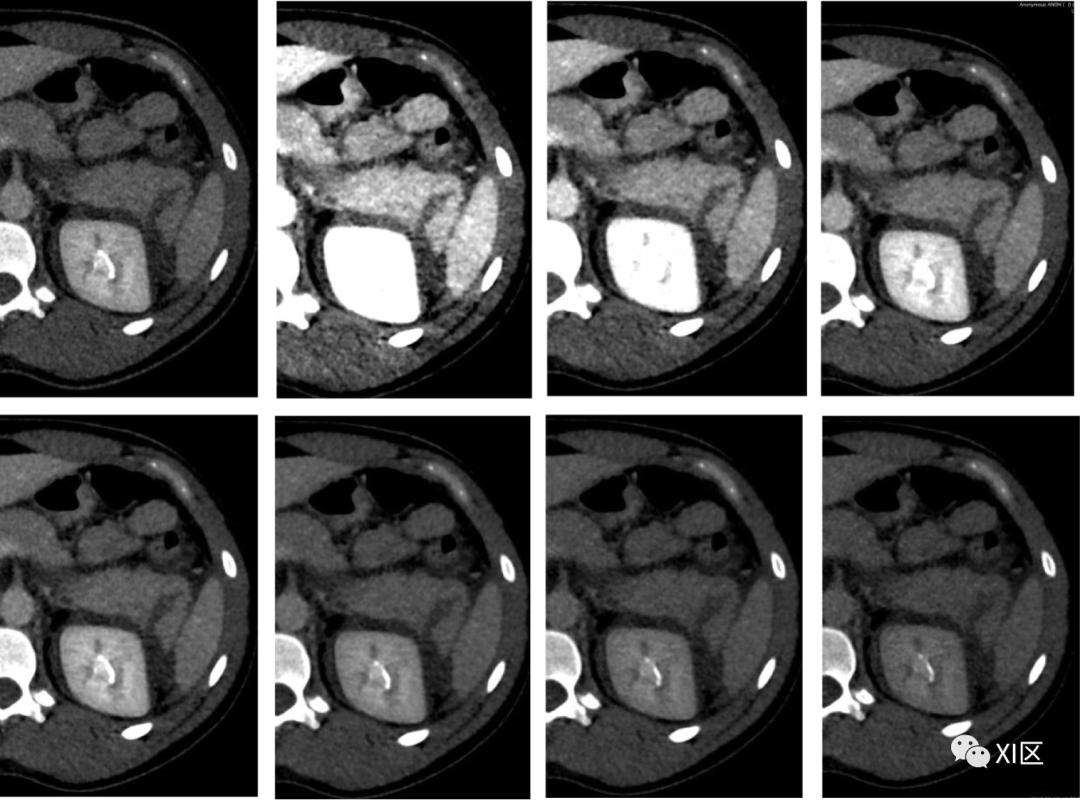

在碘图上,胃和结肠肿瘤的可检测性得到了改善(图15),恶性和良性病变的鉴别也得到了改善。碘图像也适用于急腹症患者,如小肠缺血或胃肠道出血。它们增加肠壁低衰减段的显著性,从而潜在地改善缺血的早期检测。它们还可以帮助识别造影剂外渗的细微区域,以便准确定位胃肠道出血的来源。

图15 71岁男性患有升结肠癌。显示了动脉期70 keV(a)下的虚拟单色图像和碘图(b)。碘图比单色70keV图像更显眼。(c)PET-CT图像(肿瘤的最大标准化摄取值为6.1)增强双能量CT扫描对于血管内主动脉修复术(EVAR)后的内漏检测有价值。在较低能量下获得的VMI会增加血管对比度,而晕染和金属伪影会降低图像质量。另一方面,碘图在不增加晕影的情况下提高了内漏的显著性(图16)。